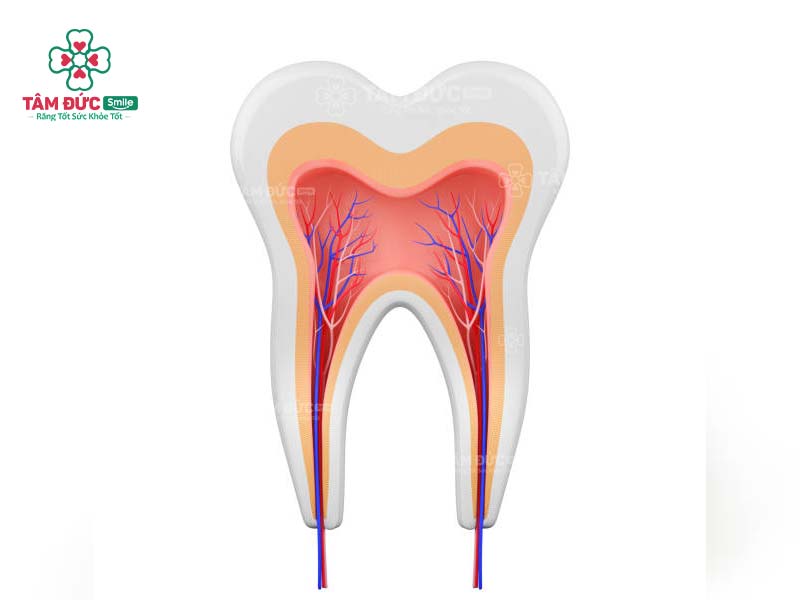

1. Tủy răng màu gì?

Tủy răng là nguồn sống của răng, có cấu trúc phức tạp và không tương đồng ở các răng. Trong trạng thái bình thường, tủy răng có màu xanh đỏ, được bao bọc bởi lớp men răng và ngà răng bên ngoài.

Trong tủy răng gồm có mạch máu và các dây thần kinh, là các thành phần nuôi dưỡng răng khỏe mạnh. Tủy răng bao gồm 2 bộ phận chính: Buồng tủy và ống tủy. Trong đó, ống tủy là những sợi mô nhỏ, thân mảnh và chia thành nhiều nhánh xuống buồng tủy. Ống tủy kéo dài từ thân răng cho đến chóp ở chân răng.

Cấu tạo tủy răng rất phức tạp, thay đổi ở từng chiếc răng, từng cá thể và độ tuổi. Số lượng ống tủy cũng không tương đồng: Răng cửa có 1 ống tủy, răng hàm nhỏ có 2 ống tủy, răng hàm lớn có 3-4 ống tủy.

Hình ảnh mô phỏng màu của tuỷ răng